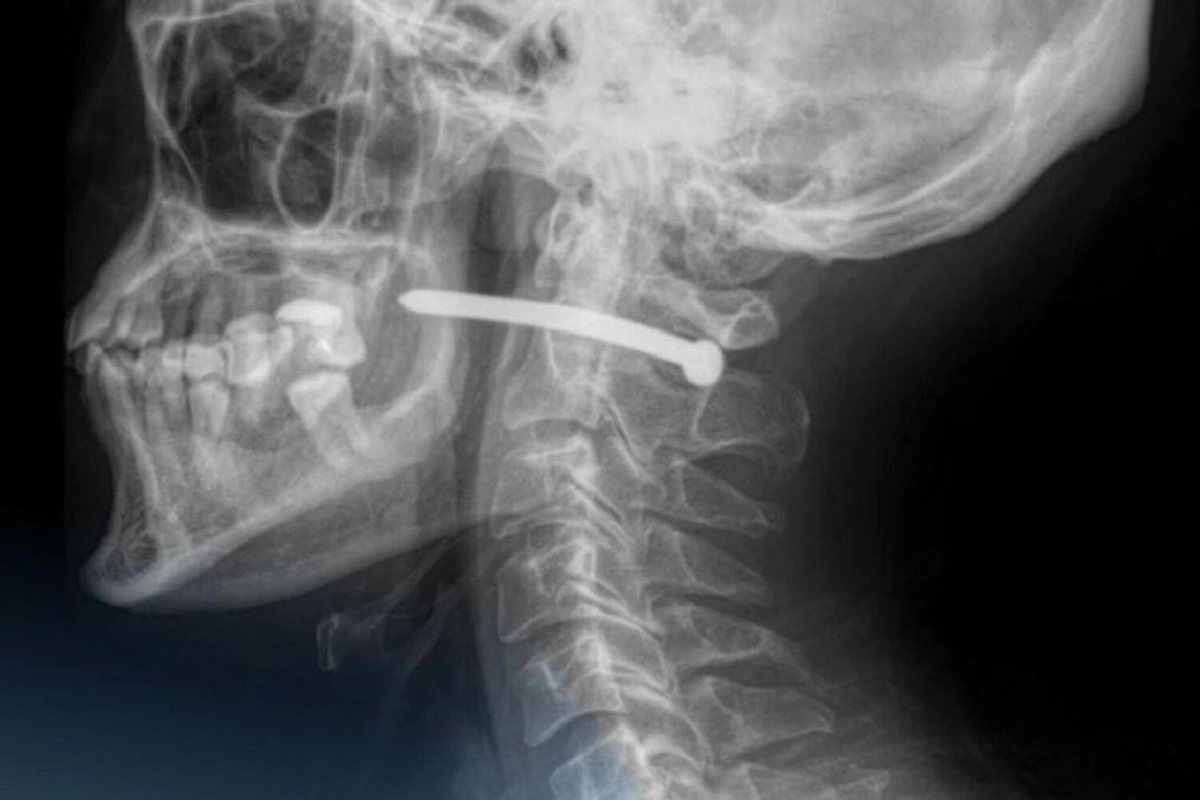

Инцидент произошел в Петропавловске. 51-летний местный житель обратился в городскую больницу скорой помощи с ранением за ухом. Как выяснилось, при проведении ремонтных работ он случайно получил травму - в него выстрелил гвоздь из пневматического пистолета.

Рентген показал, что металлический предмет прошел всего в нескольких миллиметрах от шейного отдела позвоночника. Медики подчеркнули, что мужчине невероятно повезло: ни жизненно важные органы, ни крупные сосуды не были задеты.

Хирурги извлекли гвоздь, обработали рану и наложили швы. После операции пациента отпустили домой, дав необходимые рекомендации. Врачи напомнили, что любые повреждения в области шеи крайне опасны, поскольку там проходят важные артерии, нервы, дыхательные пути и спинной мозг.